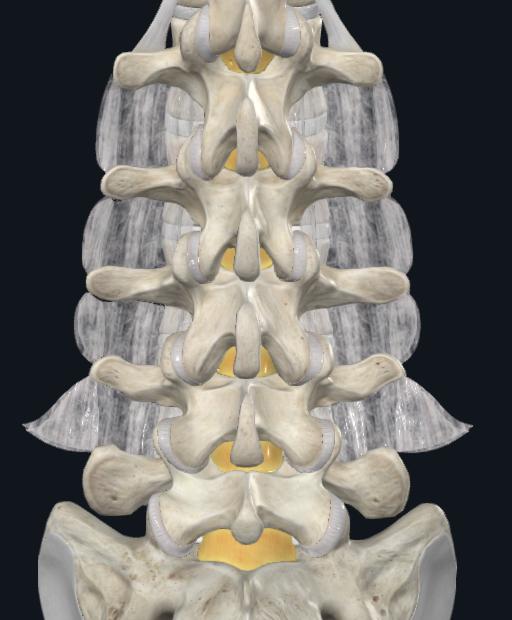

AnatomicalConsiderations

Entrypointsvarybasedonlocation

Lumbar: Confluenceofanyof:Parsinterarticularis,Mamillaryprocess,Lateralborderofsuperiorarticularfacet,Mid TransverseProcess

Thoracic: 2mm lateral and caudal to the intersection of the mid portion of facet joint and superior edge of transverseprocess.Movesmoresuperiorlywithhigherthoraciclevels

Cervical:2-3mmBelowinferioredgeofsuperiorfacet,5-6mmmedialtolateraledgeoflateralmass

Figure 6: Anatomical Variations in Entry Points of Pedicle Screw Fixation. A) General Entry points for axial/sagittal trajectoriesateachspinallevel,B)LumbarSpineRelevantAnatomy(targetshighlightedinpurple/pink),C)OptimalAngles usedforThoracicSpinePedicleScrewFixation,D)CervicalSpinePedicleScrewFixationtrajectory